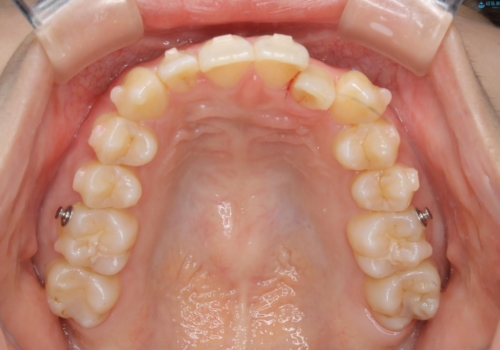

クロスバイトしている歯が深く噛み込んでおり、この歯を外に出してくる際に強い咬合力が加わると歯が失活する恐れがあることを説明し、合わせて咬筋へのボトックス注入を行いました。

下顎切歯が1本欠損しているため、上顎前歯部を少しずつストリッピングして、上下の噛み合わせ、バランスの向上を図りました。